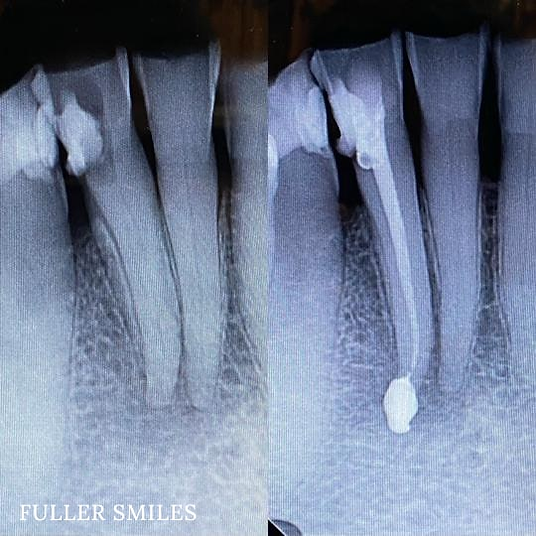

Testimonial 2

Patient presented to the office with a concern that the tooth has been causing severe constant pain that would become worse at night time. Patient presented to the office with a concern that the tooth has been causing severe constant pain that would become worse at night time. A detailed clinical exams including endodontic screening and x rays let to the diagnosis of irreversible pulpitis (infected nerve) due to gross dental caries that reached the nerve of the tooth with asymptomatic apical periodontitis (normal ligaments). Root Canal treatment was performed that included removing the caries, dead nerve tissue and disinfecting the canals with proper medication to achieve a 3D hermetic seal of the canals to save the tooth.